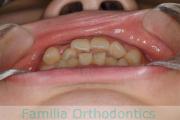

No.23V-069

- 主な症状:

- 上下顎前突

- その他の症状:

- 叢生

- 年齢:

- 25歳

- 性別:

- 女性

- 抜歯部位

- 上:

- 44

- 下:

- 主な使用装置:

- FEA 022

- 治療にかかった費用:

- 88万円

前歯のでこぼこと口元の突出感を治したいということで来院されました。上下の前歯の突出がある上下顎前突と叢生のケースでした。上下左右から小臼歯を抜歯を抜歯してマルチブラケット法にて治療を行いました。2年強、25回程度の通院が必要でした。

特に治療前に内側に入っていた上の側切歯の後戻りリスクが大きいケースです。